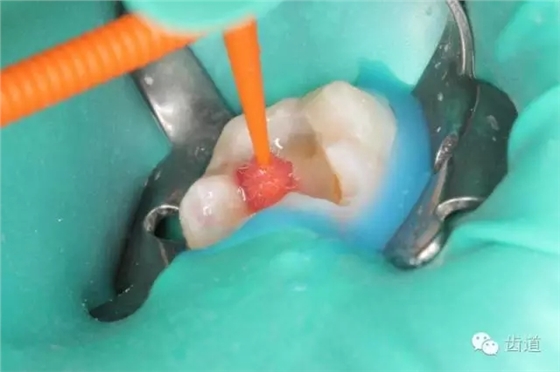

四診(2015.03.10): 主訴:復(fù)診,癥狀消失,無(wú)不適。 檢查:37暫封無(wú)缺損,探痛-,叩痛-,松動(dòng)-,牙齦無(wú)紅腫。 治療過(guò)程: 37橡皮障放置,去盡暫封,超聲清理洞形,試戴嵌體就位,分別處理嵌體及牙體粘結(jié)面,粘固,光照固化,調(diào)整咬合,修整拋光。

1. 暫時(shí)充填物完好

2. 超聲清理去除暫時(shí)充填物

3. 試戴嵌體就位良好

4. 30%磷酸算蝕牙體粘接面

5. 涂布Bisco All Bond 粘結(jié)劑 20s

6. 光照固化20s

7. 氫氟酸酸蝕修復(fù)體粘接面15s

8. Bisco Dual link 瓷處理劑涂布修復(fù)體粘接面

9. Bisco Dual link 樹(shù)脂水門汀 完成嵌體粘固

10. 術(shù)后即刻口內(nèi)照片